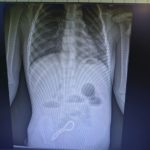

Рязанские хирурги спасли трехлетнего малыша, который проглотил магнитный браслет

Как сообщает министерство здравоохранения Рязанской области, трехлетний ребенок проглотил магнитный браслет из 30 шариков.